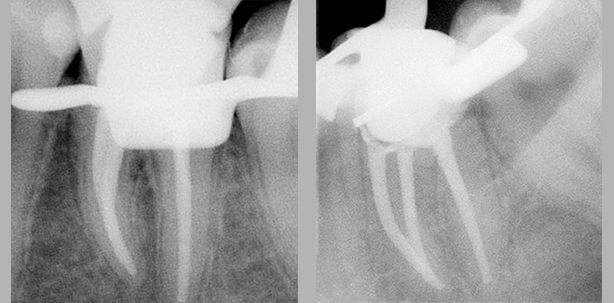

Im Fall der 28 Jahre jungen Patientin führte die inadäquate Ästhetik sowie ein taktiles Missempfinden, verursacht durch scharfe Kanten an der vorhan­denen Füllung des Zahnes 36, zur ­zahnärztlichen Konsultation in meiner Sprechstunde. Allgemeinanamnestisch war sie unauffällig und unterstand keiner Medikation. Die eingehende Untersuchung ergab einen retinierten Zahn 28, eine Sekundärkaries an 22 sowie eine ausgedehnte insuffiziente Glasionomerfüllung an 36. Im angefertigten Orthopantomogramm und Zahnfilm war ersichtlich, dass diese den gesamten Raum des Pulpenkavums einnahm und an den Zustand nach Pulpotomie erinnerte. Der Zahn reagierte weder auf thermische noch auf elektrische Reizung sensibel. Eine apikale Aufhellung war nicht sichtbar (Abb. 1). Aufgrund der Pulpanekrose musste der Zahn ­endodontisch therapiert werden. Nach Entfernung der Füllung wurde 36 mittels eines All-in-one-Adhäsivsystems und eines gebräuchlichen Kompositmaterials für die Aufnahme eines Kofferdams wieder aufgebaut. Unter Kofferdamisolierung wurde die Zugangskavität präpariert. Drei Kanaleingänge (mb, ml, d) konnten gefunden und mithilfe von Gates-Glidden-Bohrern erweitert werden. Der Verlauf des natürlichen Pulpenkammerbodens war bereits iatrogen verändert worden und stellte sich als plane Fläche dar (Abb. 2).

Nach Wiedereröffnung der Zugangs­kavität und initialer Spülung der Kanäle ergab die Endometrie Werte von 19 mm für den distalen und 21,5 mm für die beiden mesialen Kanäle. Auf diese Arbeitslängen fand nun die maschinelle Aufbereitung mit den vollrotierenden F360-Feilen (Komet) statt. Ich ging in zwei Schritten über ISO 35 zur Finalfeile der Größe ISO 55 vor. Mit formkongruenten Masterpoints desselben Herstellers fertigte ich anschließend zwei Masterpointaufnahmen an (Abb. 3 und 4), da aufgrund der röntgenologischen Überlagerung der mesialen Guttaperchaspitzen eine weitere Aufnahme von distoexzentrisch notwendig war. Die Entfernung des Smear-layers erreichte ich mit 17%iger EDTA-Spülung über mehrere Minuten. Dem angewendeten Spülprotokoll im Rahmen einer Primärbehandlung folgend wurde die abschließende Spülung mit NaOCl durchgeführt und die Wurzelkanäle anschließend getrocknet. Die Wurzelkanalfüllung erfolgte mit den angepassten Masterpoints, AH-Plus Sealer und mittels lateraler Kondensation (Abb. 5). Die Kavität wurde adhäsiv verschlossen und es folgte die röntgenologische Kontrolle, wobei ebenfalls ein exzentrischer Strahlenverlauf zur optimalen Beurteilung derselben notwendig war (Abb. 6).